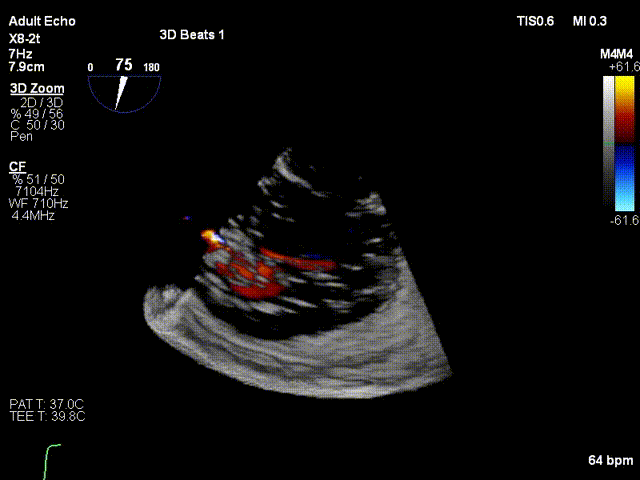

术前与术后30天三尖瓣反流比较